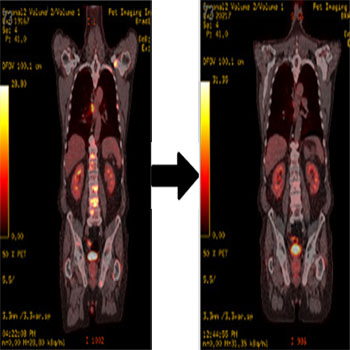

We present a 71-year-old male who was diagnosed with BC in March 2012. The patient underwent a left modified radical mastectomy with the finding of a 2.2 cm high grade invasive ductal carcinoma ER+, PR+, HER 2/neu negative, KI 67 25%, with 2 out of 24 axillary lymph nodes involved by carcinoma. He received adjuvant chemotherapy with dose-dense Adriamycin and Cyclophosphamide followed by 12 weeks of paclitaxel. He received adjuvant radiation therapy to the left chest wall and regional lymphatics (5040 cGy delivered in 28 fractions). Patient started adjuvant ET with tamoxifen in November 2012. Genetic testing revealed absence of deleterious mutations for the BRCA1 or BRCA2 genes. After doing clinically well for nearly four years, he developed progressive back and pelvic pain. Based on these findings, systemic recurrence of disease was suspected.  18F-fluorodeoxyglucose-positron emission tomography-computed tomography (FDG-PET/CT) scan (Figure 1A) demonstrated new multiple FDG avid mediastinal and right hilar adenopathy, mixed lytic and sclerotic bone metastases scattered in the axial and appendicular skeleton involving sternum, bilateral ribs, scapula, spine, pelvis and bilateral proximal femora. Tumor markers demonstrated elevation in CA 15-3 level to 109 U/mL (reference range: < 32 U/mL) and CEA level to 25 ng/mL (reference range: < 2.5 ng/mL). Bone biopsy of the right pubic area, revealed metastatic carcinoma consistent with a breast primary (ER +, PR+, HER 2/neu negative). The patient was started on therapy for stage IV ER+/HER2 negative breast cancer. His treatment consisted of a fulvestrant loading dose followed by a monthly 500 mg intramuscular (IM) dose in addition to oral palbociclib 125 mg given once daily for 3 weeks followed by 1 week off over a 28-day cycle. He also received intravenous zolendronic acid 4 mg monthly for the prevention of skeletal related events. Soon after starting therapy, the patient demonstrated symptomatic improvement of his bone pain. FDG-PET/CT scan following 3 months of systemic therapy is shown on Figure 1B. Tumor markers decreased in levels; CA 15-3 level was 49 U/mL and CEA level was 4.4 ng/mL. Treatment was well tolerated with minimum toxicity. Absolute neutrophil count remained above 1.5 1000/ uL throughout therapy.

Figure 1A and 1B: Radiographic response following 3 months of systemic therapy. A) FDG-PET/CT demonstrating new multiple FDG avid mediastinal and right hilar adenopathy, mixed lytic and sclerotic bone metastases scattered in the axial and appendicular skeleton. B) FDG-PET/CT demonstrating significant improvement with decreased FDG uptake of pulmonary, nodal and osseous metastases.